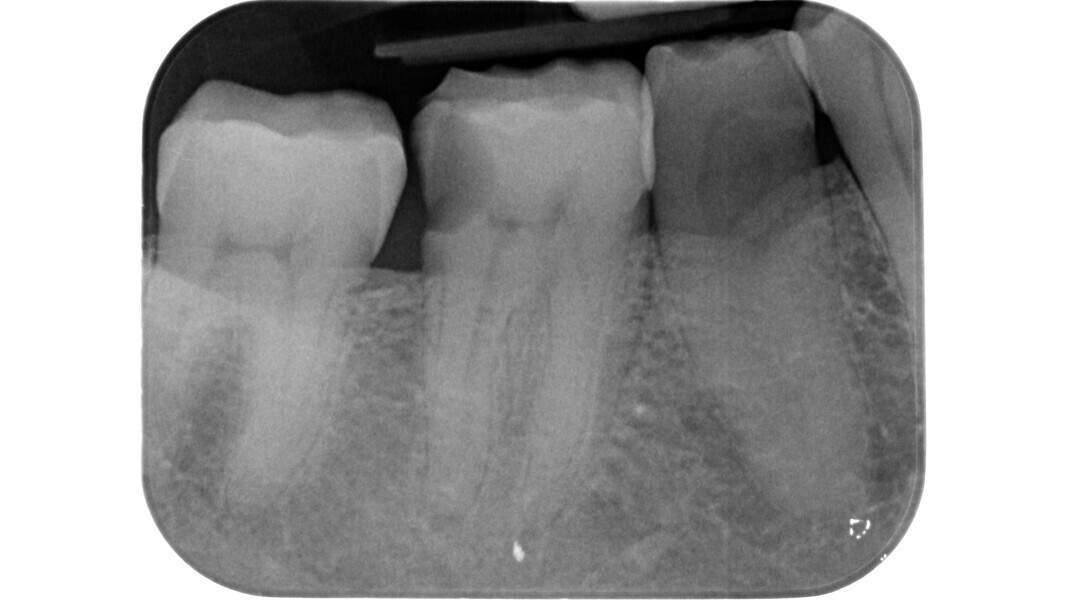

L’étape suivante est la phase de localisation et celle-ci peut s’avérer très difficile, surtout dans les dents calcifiées. Dans ce cas, le praticien doit laisser de côté les instruments rotatifs diamantés et recourir à divers dispositifs spéciaux.

Parmi ces lois, certaines revêtent une importance clinique fondamentale. Par exemple, dans des conditions plus difficiles, telles que dans le cas d’une préparation dentaire prothétique, où les points de repère classiques sont perdus, la connaissance des trois premières lois nous permet de tracer une cavité d’accès qui suit le contour de la dent, et de repérer les orifices à l’intérieur de cette zone. D’un point de vue embryogénétique, la couronne dentaire est la projection du développement du tissu pulpaire.

Le principe du diamant fait référence à l’utilisation d’un certain type de fraise diamantée pour la phase de pénétration, en particulier dans les molaires supérieures et inférieures, ainsi que dans les prémolaires supérieures biradiculées. Deutsch8–9 associe des mesures morphologiques à la relation entre la surface occlusale, la hauteur, la position du plafond et du plancher de la cavité dans les dents pluriradiculées. Dans ces éléments, le plafond de la cavité pulpaire est situé au niveau de la JAC.

Dans les molaires, la distance entre la pointe d’une cuspide et le plafond de la cavité pulpaire est d’environ 6,3 mm, tandis que dans les prémolaires supérieures, elle est de 6,94 mm. La cavité pulpaire a une hauteur d’environ 1,5 à 2 mm et la distance moyenne entre le plancher de la cavité et la furcation est d’environ 3 mm (Tableau 1) (Fig. 13).